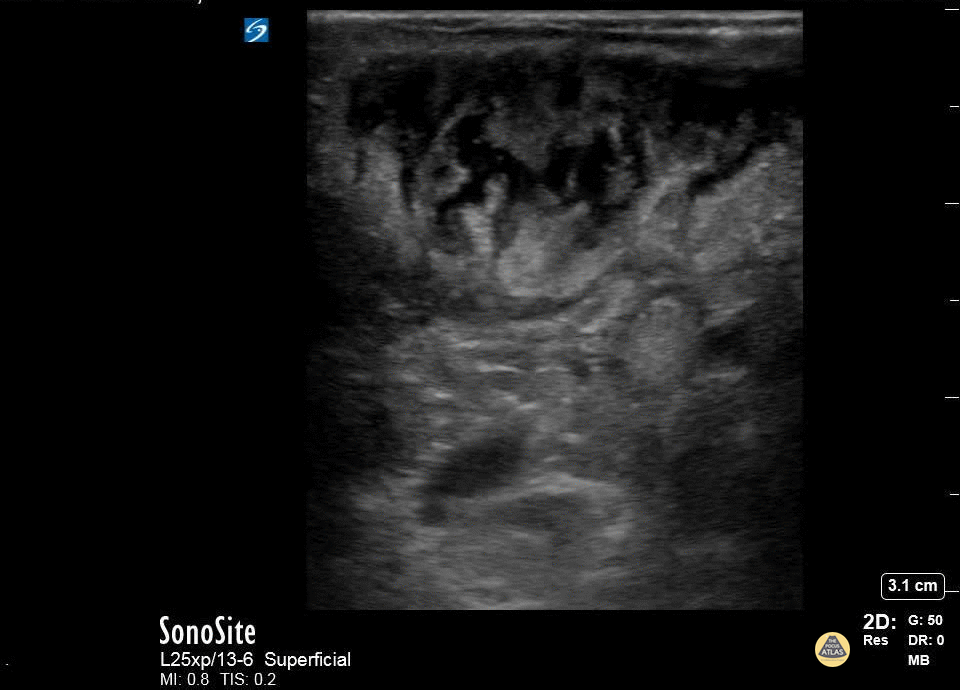

Soft Tissue - Abscess Identification

A patient with cerebral palsy and quadriplegia presented with her mother for evaluation of a fluctuant mass in her right axilla. Ultrasound imaging of the mass showed an abscess with multiple septations. The abscess was incised and drained, and the patient was discharged on antibiotics. Katy Van Donselaar, Emergency Medicine Resident Christopher Heberer, Emergency Medicine Resident Simhadri Botta, 4th year Medical Student